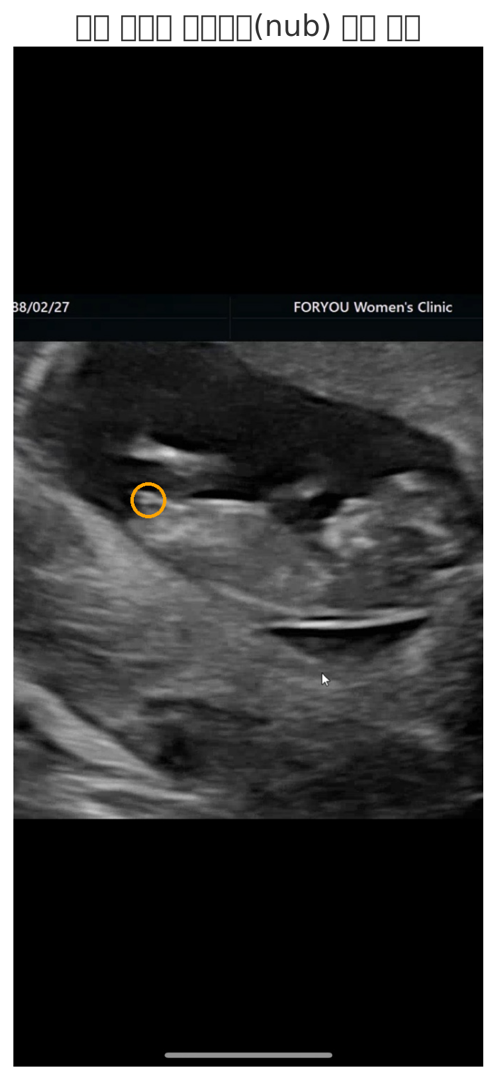

생식돌기 원을 쳐놓은 부분안에 있는게 맞나요?

제가 표시한 부분에 있는게 생식돌기가 맞나요?

네. 그렇게 보이네요. 딸 각도 같아요